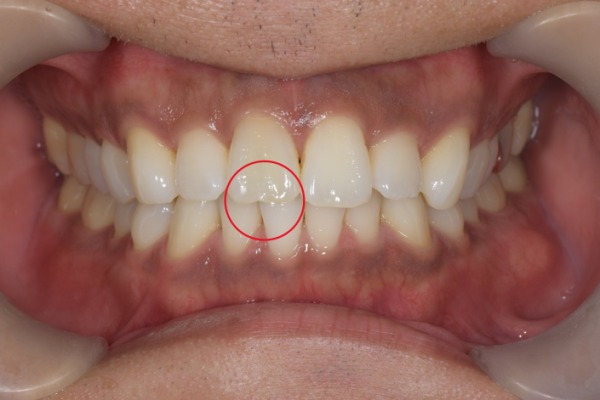

治療前の噛んだ状態の写真です。

患者様は歯ぎしり食いしばりがあり、マウスピースを睡眠時に使用して予防していました。しかし神経の治療をしてから長期間経過していたこともあり、歯質にヒビがあることを確認しました。